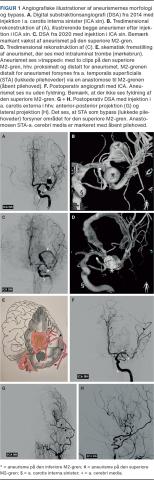

En 29-årig mandlig ryger med hyperkolesterolæmi og Arnold-Chiaris malformation fik i 2014 påvist to aneurismer på venstre a. cerebri media (MCA) beliggende efter MCA’s første deling (M2-grene) (Figur 1A+B). Begge målte 10 mm i største diameter og var beliggende på hhv. superiore og inferiore M2-gren. Aneurismet på den superiore M2 var fuciformt (involverede > 50% af karrets cirkumferens). Pga. aneurismernes størrelse og patientens unge alder anbefalede man lukning for at forebygge ruptur og subaraknoidalblødning.

I juni 2014 blev der foretaget coilembolisering af aneurismet på den inferiore M2, mens der samtidig blev lagt en stent over aneurismet på den superiore M2. En kontrolundersøgelse i 2016 viste, at det coilede aneurisme var stort set lukket, mens det superiore fortsat var åbent. En kontrolundersøgelse i 2018 viste, at det det superiore aneurisme var ved at trombosere, men den åbne del var i vækst. Dette blev tolket som, at stenten var begyndt at have effekt, og man regnede med, at aneurismet langsomt ville lukke over de kommende år.

I foråret 2020 klagede patienten over synssløring og hovedpine. Han fik konstateret bilateralt papilødem. Ved en CT af hjernen påvistes en proces med udtalt omgivende ødem ved aneurismets placering. Angiografi viste yderligere vækst af både den tromboserede og den ikketromboserede del af aneurismet (Figur 1C + D). Det var nu vokset til over 3 cm i diameter.

Det blev vurderet, at den bedste behandling var at udelukke det aneurismebærende kar fra den øvrige cerebrale cirkulation. Patienten blev derfor opereret med indsyning af en cerebral bypass fra a. temporalis superficialis til superiore M2/3-MCA-gren distalt for aneurismet (Figur 1E). Herefter blev aneurismet »trapped« ved lukning af det aneurismebærende kar proksimalt og distalt for aneurismet (Figur 1E). Slutteligt blev aneurismet åbnet og tømt for trombemateriale for at skabe dekompression.

Efter operationen tilkom et reaktivt ødem, der medførte en stigning af det intrakranielle tryk (ICP). Der blev derfor foretaget dekompressiv hemikraniektomi (fjernelse af en ca. 10 cm stor knogleplade fra den ene side af kraniet) for at sænke ICP. Herefter blev patienten holdt i respirator. Efter ca. 14 dage kunne han vækkes, og knoglepladen kunne replaceres. Han havde en let højresidig hemiparese og blev udskrevet til genoptræning. Ved kontrol tre måneder efter operationen var han i velbefindende uden hovedpine eller synsforstyrrelser. Den højresidige hemiparese var fuldt remitteret. Angiografi viste åbenstående bypass med flowsubstitution til venstre hemisfære og eksklusion af aneurismet (Figur 1F-H).